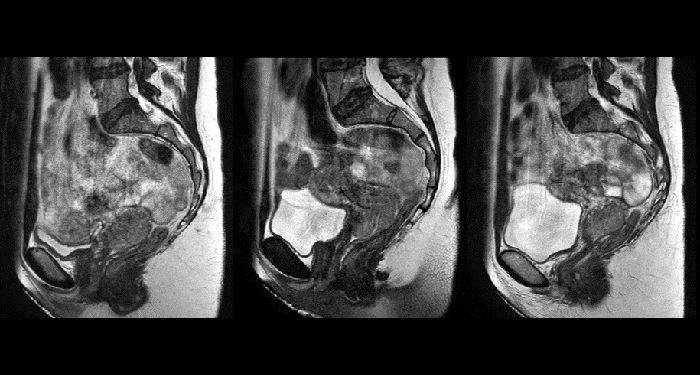

With its exceptional soft-tissue visualization capabilities and wide range of image contrasts, MRI has become a powerful tool to help more precisely define tumor boundaries. This is particularly important as it has been established that there is a high degree of uncertainty in target volume delineation, and it is even reported to represent the largest uncertainty in the entire radiotherapy process for most tumor sites**. Better visualization of the target area and nearby organs-at-risk is a key factor in enhancing target volume delineation. MRI’s expanding role also can be attributed to its functional imaging capabilities, which can inform both target characterization and treatment response.

With its superior soft tissue contrast compared to CT, MRI offers exquisite visualization of tumor boundaries and proximity to nearby critical structures.

The ability to tune contrasts can provide even more valuable information about tumor characteristics and tumor extent to facilitate enhanced delineation, and also provides possibilities for dose boosting strategies.

In addition to anatomical imaging, MRI offers the ability to obtain functional information that is beneficial for tumor detection and delineation, and for response monitoring.